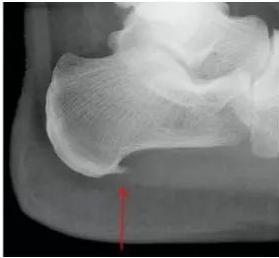

图1.跟骨骨刺(图片来源于网络)

此结构最薄弱的部分就是"弓弦"与"弓体"相交接的地方,也就是足跟处,正是临床上最常见的骨刺发生部位。这个地方反复受到刺激和损伤,导致了在应力方向骨刺的形成。所以我们仔细视察X光片会发现,骨刺方向是水平而不是垂直向下的。通过骨质增生的方式,增加韧带与骨骼的接触面积,减少骨骼单位面积上的受力,使得接触面更加稳定,重头变得平衡。